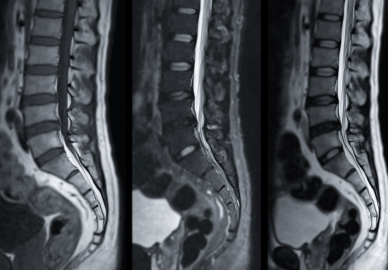

Röntgen, MR & Ultraljud

Kan vara en del av vägen till din diagnos.

Som en del av din utredning på Kroppia gör vi en noggrann klinisk bedömning av om bilddiagnostik är nödvändig för att fastställa rätt diagnos eller säkerställa att behandling kan ske tryggt.

Vi börjar alltid med en grundlig klinisk funktionsanalys. Bilddiagnostik används som ett precisionsverktyg när vi behöver bekräfta fynd eller utesluta bakomliggande orsaker som inte syns vid en manuell undersökning.

Vi går igenom dina röntgen- eller MR-svar tillsammans. Det viktigaste är hur bilderna korrelerar med din biomekaniska status, så att vi kan utforma en träffsäker behandlingsplan.

Tolkning & Åtgärd